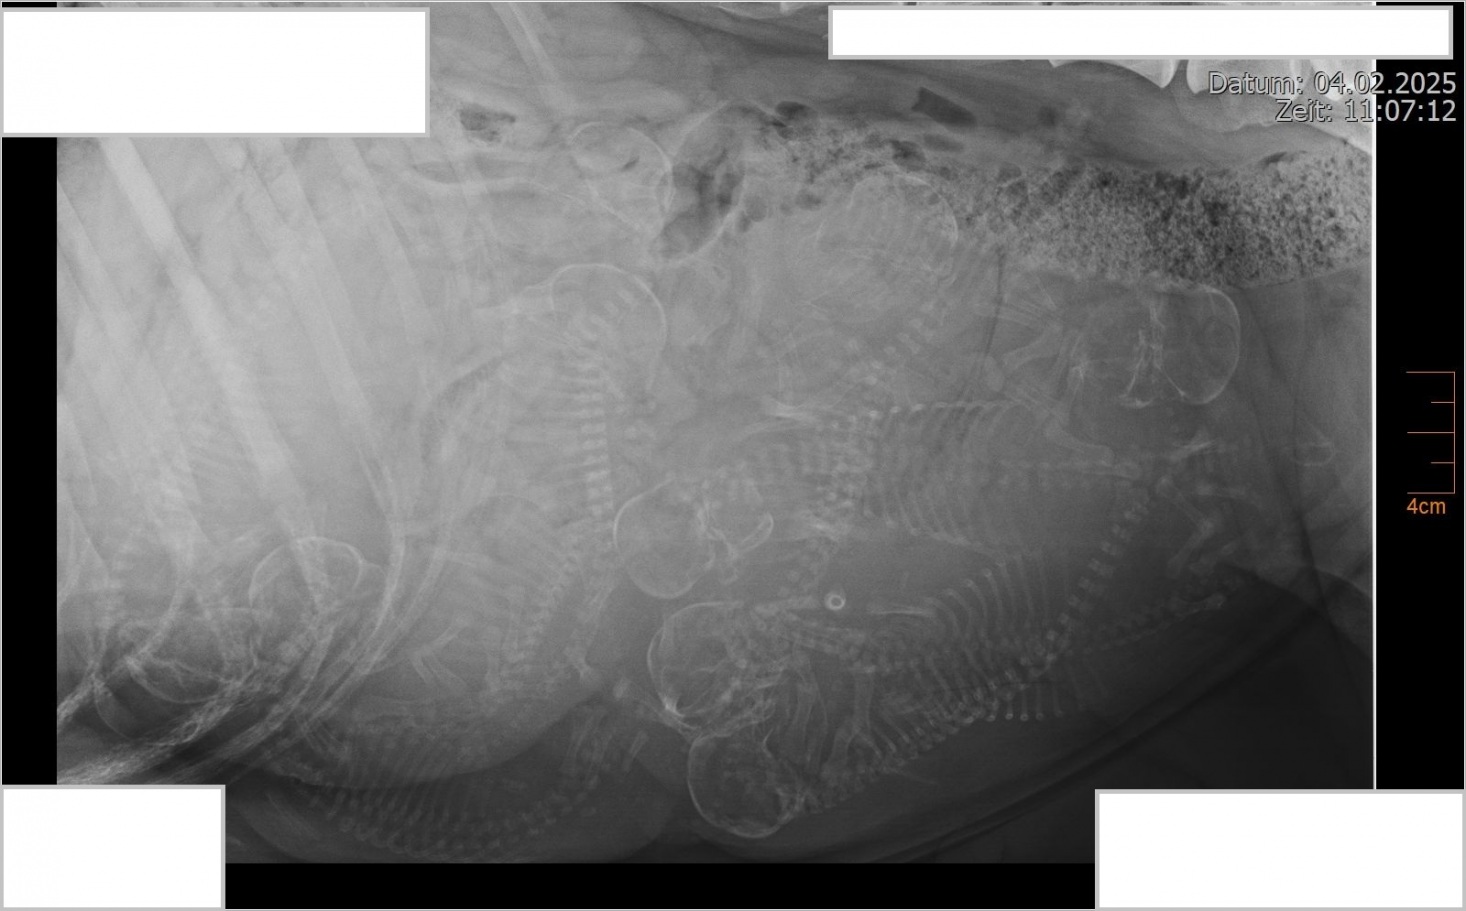

So langsam wird es eng in Bailey's Bauch, wir freuen uns so sehr auf die kleinen Welpen!